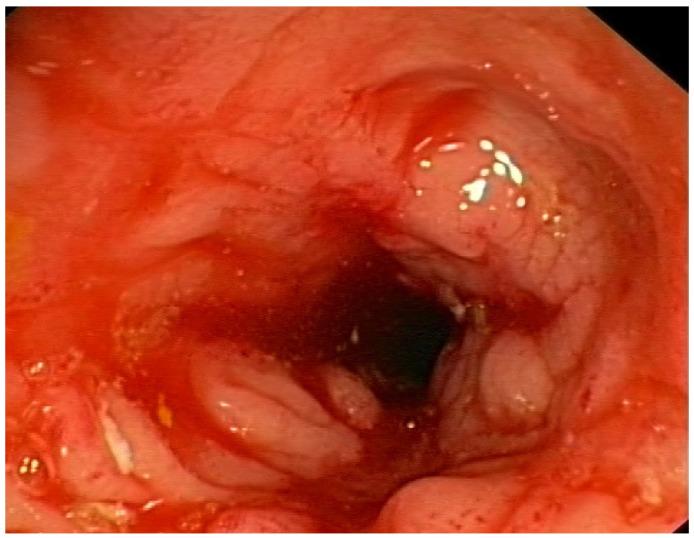

A significant correlation (-value < 0.05) between CD and bacterial metabolites was obtained for three of eight tested SCFAs; acetic acid (reduced in CD; FC 1.7; AUC = 0.714), butyric acid (increased; FC 0.68; AUC = 0.717), 2MeBA (FC 1.168; AUC = 0.702), and indoxyl (FC 0.624). The concentration of CA (FC 0.82) and choline (FC 0.78) in plasma was significantly disturbed according to the biological treatment. Choline level (FC 1.28) was also significantly disturbed in the patients treated with glucocorticoids. In total, 68.97% of Crohn's patients presented extraintestinal manifestations (EIMs) of Crohn's disease, mainly osteoarticular complications. The level of BA was statistically significantly elevated in patients with extraintestinal (FC 0.602) manifestations, while in the group of patients with osteoarticular complications, a significant difference in the level of betaine (FC 1.647) was observed.

在8种测试的短链脂肪酸中的3种(乙酸(在克罗恩病中减少;FC 1.7;AUC = 0.714)、丁酸(增加;FC 0.68;AUC = 0.717)、2 - 甲基丁酸(FC 1.168;AUC = 0.702)和吲哚酚(FC 0.624))中,克罗恩病与细菌代谢产物之间存在显著相关性(P值<0.05)。根据生物治疗,血浆中牛磺酸(FC 0.82)和胆碱(FC 0.78)的浓度受到显著干扰。在接受糖皮质激素治疗的患者中,胆碱水平(FC 1.28)也受到显著干扰。总共有68.97%的克罗恩病患者出现克罗恩病的肠外表现(EIMs),主要是骨关节并发症。在有肠外表现(FC 0.602)的患者中,牛磺酸水平在统计学上显著升高,而在骨关节并发症患者组中,观察到甜菜碱水平有显著差异(FC 1.647)。